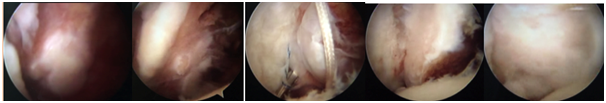

From left to right, initial aspect of the lesser tuberosity adhered to soft tissue, the aspect after debridement and mobilization, passage of sutures using "Bird Beak", partial reduction of the fragment and final appearance after final fixation with 3 anchors. The first suture anchor was placed in the inferior region of the medial margin at the fracture site, with the subscapularis tendon penetrated immediately adjacent to the bone-tendon interface at the most inferior aspect, using a bird-beak passer. The second anchor was placed in the medial margin of the fracture area in a more superior position, with the suture passing through the most superior aspect of the subscapularis tendon. The third anchor was placed in the most lateral aspect of the fracture area and its suture threads were passed through the bony fragment of the lesser tuberosity to ensure its fit in the fracture area. In addition, the threads of this third anchor were used to perform tenodesis of the long head of the biceps. Tenotomy was only performed after the bone repair and tenodesis. Checking was done through the anterolateral port. In the immediate postoperative period, the shoulder was immobilized with a sling for four weeks before the patient started physiotherapy. It has now been two and a half years since the operation and the patient has shown significant improvement. Of note, the DASH score decreased to 8.3, the UCLA Shoulder Score increased to 34, the SF-36 Score increased to 83.8 and the VAS score decreased to 2. All clinical tests for subscapularis lesions were negative at the most recent evaluation (Figures 4 & 5).

Figure 4 Postoperative Resonance Imaging. Anatomic consolidation.

Figure 5 Patient’s physical examination with negativity for the subscapular tests.